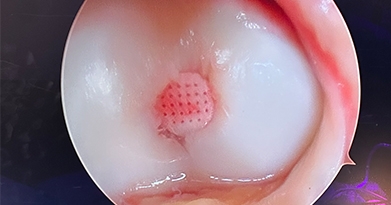

Arthroscopic surgery, is a surgical procedure to visualize, diagnose, and treat problems inside a joint using a specialized instrument known as an arthroscope. An arthroscope is a fiberoptic tube that contains a small lens or camera and a lighting system to magnify and illuminate structures inside a joint.

Orthobiologics are natural substances such as cells, tissue, blood components, and growth factors that are harnessed to aid in the treatment of orthopedic injuries or conditions. They may be used to replace lost tissue, stimulate regeneration and healing, reduce pain and inflammation, and improve joint function.